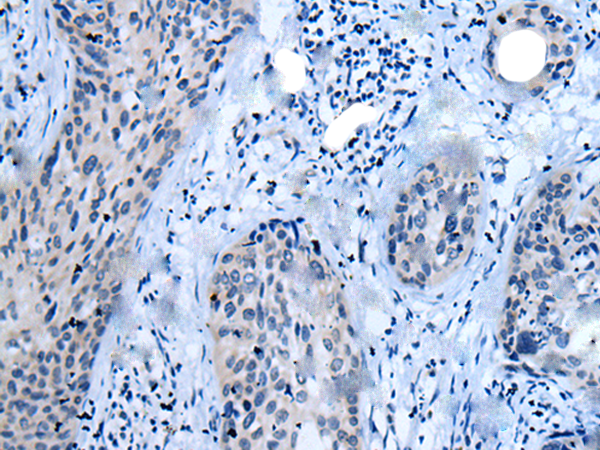

IHC positive control: |

Human cervical cancer |